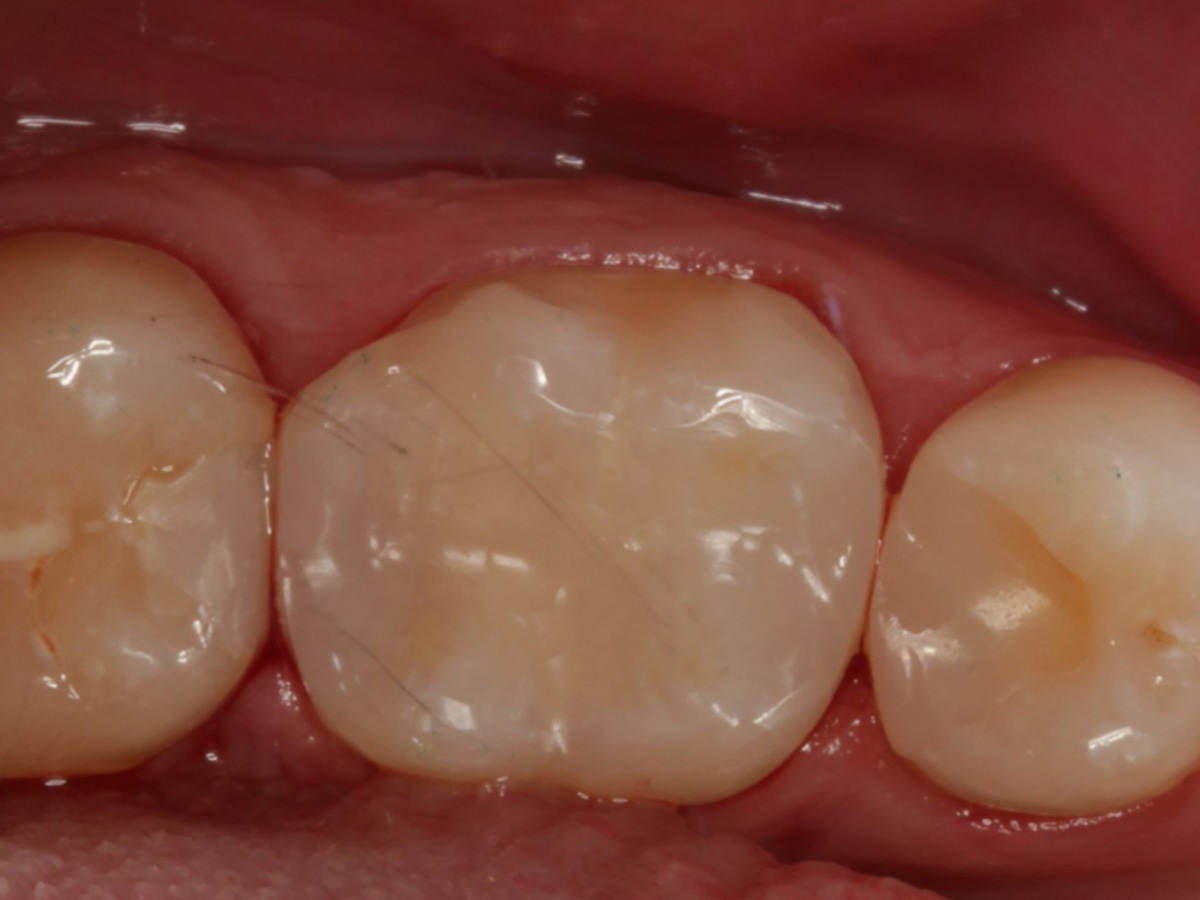

Abbildung 22

Fertige Restauration Zahn 46